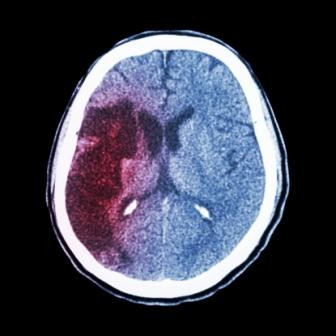

Het dagelijks gebruik van 0,8 mg foliumzuur geeft een aanzienlijke vermindering van het risico op een CVA. Het effect is het grootst bij personen met de laagste serumconcentratie foliumzuur. Foliumzuur lijkt daarom een belangrijke aanvulling bij de preventie van CVA’s bij patiënten met hypertensie…